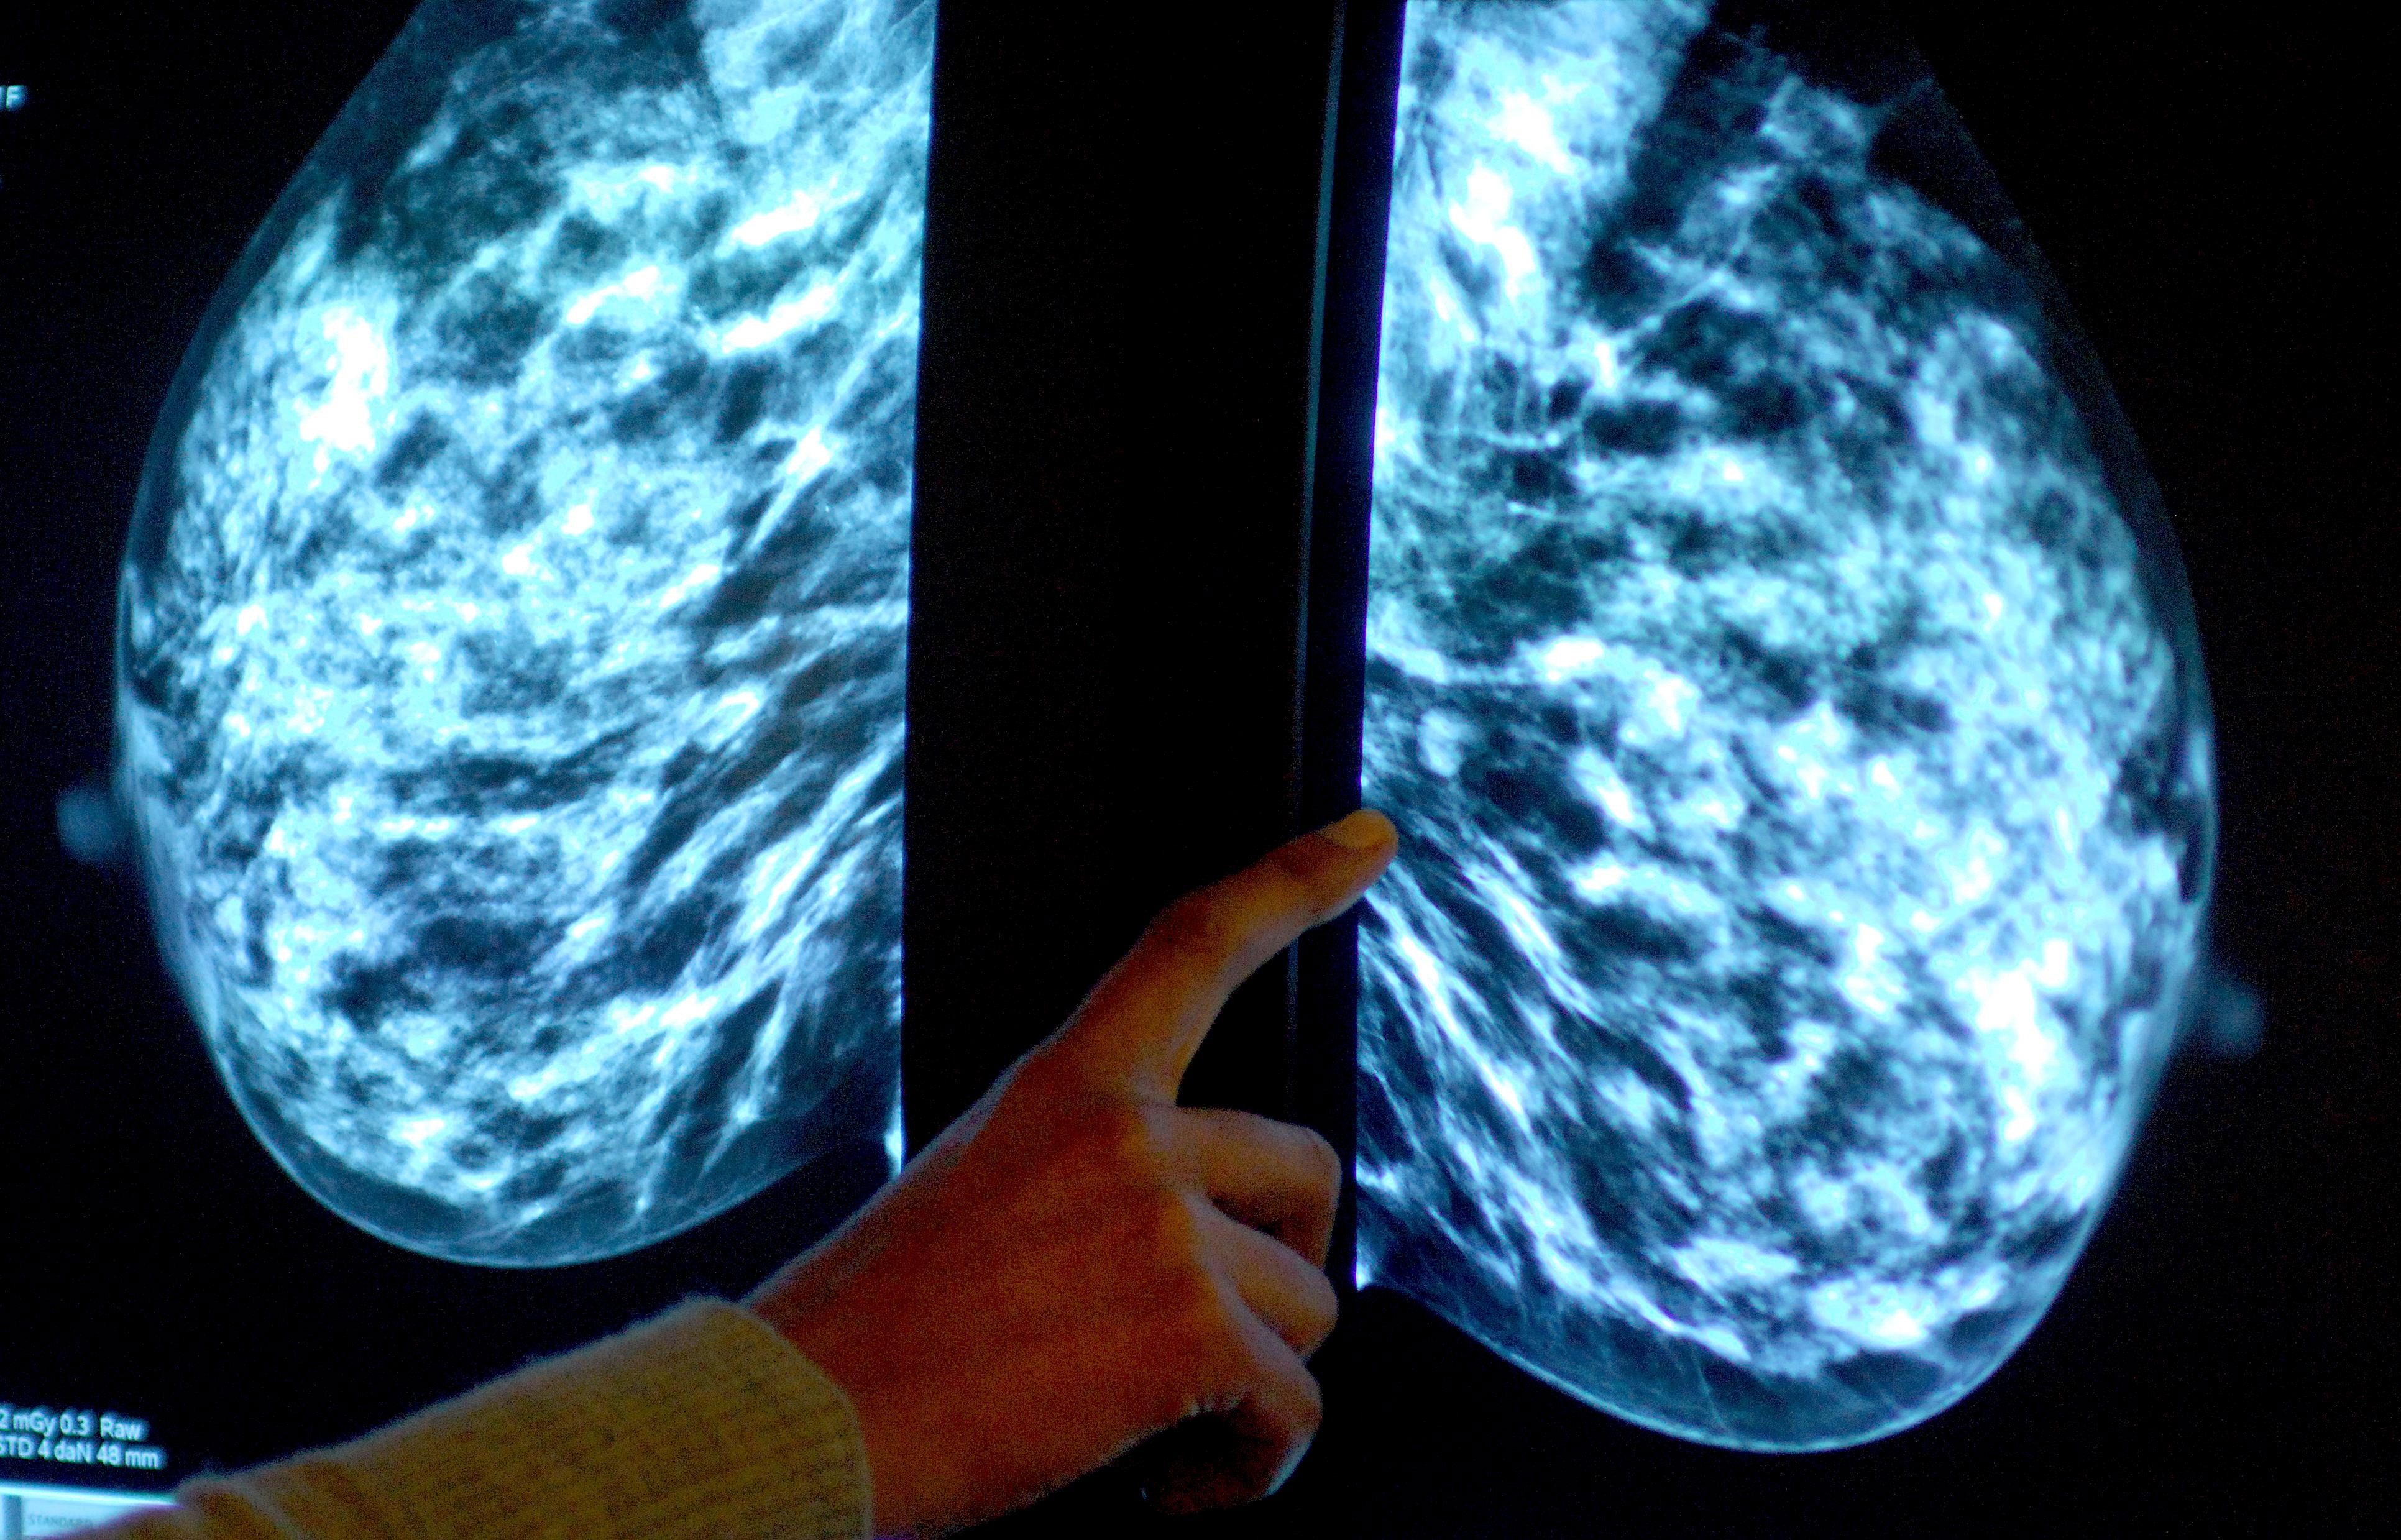

The screening program sees women aged between 50 and 71 invited every three years to undergo a mammogram (X-ray) designed to detect cancers that are too small to see or feel.